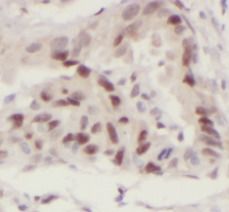

Immunohistochemistry of paraffin-embedded human lung cancer tissue using FNab08131(SP1 antibody) at dilution of 1:50